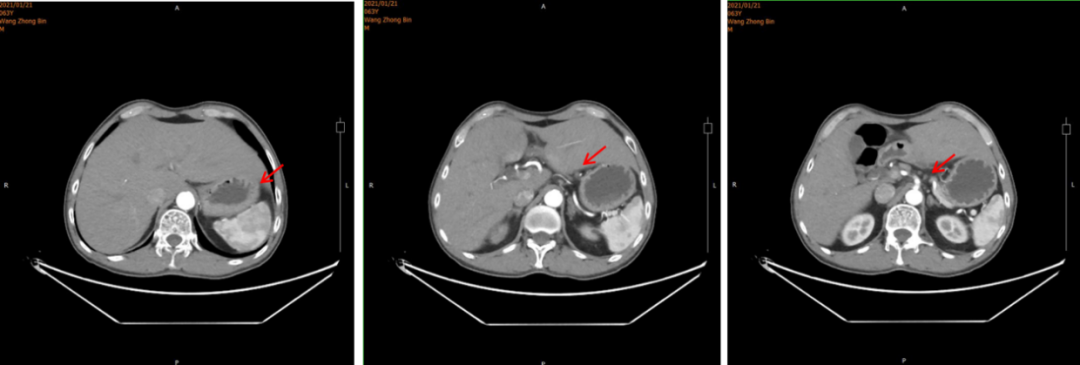

▌病例作者:大连医科大学附属第一医院 李颖 教授 ▌点评专家:大连医科大学附属第一医院 张洁 教授 编者按 ●我国是胃癌大国,根据世界卫生组织国际癌症研究机构(IARC)发布的2020年中国最新癌症负担数据:2020年中国癌症新发病例457万例,其中胃癌48万例位居第三;2020年中国癌症死亡人数300万,其中胃癌37万,位居第三[1]。70%的胃癌患者确诊时为局部进展期或进展期胃癌。其中HER2阳性胃癌是一类高度异质性肿瘤,侵袭性强、复发率高、预后不良。国内胃癌HER2阳性率的多中心研究结果显示,中国人群胃癌HER2阳性率为12~13%。ToGA[2]研究证实,曲妥珠单抗联合化疗能显著提高HER2过表达晚期胃癌患者治疗反应率,改善患者生存状况,因此曲妥珠单抗被推荐用于HER2过表达晚期胃癌的一线治疗。肝脏是胃癌血行转移最常见的靶器官,胃癌肝转移的总体发生率约9.9%~18.7%。本文通过一例赫赛汀®转换为汉曲优®治疗HER2阳性晚期胃癌伴肝转移的病例,向大家介绍汉曲优®(曲妥珠单抗)在治疗HER2阳性晚期胃癌伴肝转移患者的临床获益情况。(注:本文中汉曲优®为复宏汉霖研发生产的曲妥珠单抗) 病史简介 患者:王某,64岁,男,身高180cm ,体重60kg ,BMI 18.52。 主诉:胃癌姑息术后1年余。 既往史:既往体健,否认吸烟史、饮酒史。 家族史:否认家族性遗传病、传染史。 查体:全身皮肤粘膜无黄染,全身浅表淋巴结不大,腹部可见手术瘢痕,质软,无压痛,肝脾肋下未及,未触及包块,移动性浊音阴性。 ▌影像学检查: 2021年1月21日腹部CT:胃窦癌征象,伴胃周、腹膜后增大淋巴结,请结合临床;肝右叶肝内胆管结石或钙化灶;左侧肾上腺强化不均。 图1.腹部CT 2021年1月22日胃镜示:胃窦环幽门见一溃疡型病变,致管腔狭窄,镜身无法通过。 图2. 胃镜 ▌肿瘤基本病理: 2021年1月25日:全麻下腹腔镜姑息性远端胃大部分切除D2廓清 B-Ⅱ+Braun消化道重建肝部分切除术。术中见:肝左外叶见1枚约1*0.5cm灰白结节,肿瘤位于胃下部,大小8*6cm,侵及胰腺被膜,NO.6组淋巴结肿大。 ▌胃术后病理: 胃溃疡型中低分化管状腺癌,大小4.7*3.7cm,侵及全层,脉管癌栓,神经侵犯;纤维脂肪组织内见淋巴结转移一枚,送检(6、7.8a、9组)淋巴结见转移癌(5/17),并见癌结节一枚。送检(1.3组、4sb组)淋巴结未见转移癌(0/6)。 ▌免疫组化: GST-π:(+),HER-2:(3+),Ki67:(+80%),MLH-1:(表达),MSH-2:(表达),MSH-6:(表达),PMS-2:(表达),P53/ target=_blank class=infotextkey>P53:(突变型)。 ▌肝术后病理: 肝内见中分化管状腺癌,大小为0.9*0.6*0.7cm,结合病史及免疫组化结果考虑为胃腺癌转移来源,累及肝被膜,未见明确脉管及神经侵犯。免疫组化:ARGINASE-1(-)、CDX-2(少许+),CK19(+)、CK20(-)、CK7(+)、GPC-3(部分+)、Hep-par(少许+)、Ki67:(+75%)、muc-5AC(+)、SATB2(-)、villin(+)。 ▌术后病理: 胃溃疡型中低分化管状腺癌淋巴结转移(图3左),肝内见中分化管状腺癌考虑为胃腺癌转移来源(图3右)。 图3 术后病理 诊断:胃癌姑息术后(pT3N2M1)PLVN+、Her-2过表达、pMMR型,同时性肝转移癌术后,肝转移癌(肝左叶单发)。 治疗经过 2021年1月25日:全麻下腹腔镜姑息性远端胃大部分切除 D2廓清 B-Ⅱ+Braun 消化道重建肝部分切除术。 2021年3月5日术后化疗时上腹部增强MRI发现疾病进展,出现新发肝转移癌。MRI示:胃体积减小,肝脏局部体积减小,肝左叶见一类圆形轻度环形强化影,平扫显示不清,最大径约16.6mm。诊断建议:肝、胃术后改变,肝左叶环形强化影,新发肝转移。(图4) 图4. 上腹部增强MRI 2021年3月3日起行一线曲妥珠单抗联合AS方案化疗: 具体:赫赛汀®:440mg 首周期剂量,360mg 后续周期剂量,7周期,因经济原因和患者体重下降原因调整为汉曲优® 300mg 继续完成后续治疗,目前共完成靶向治疗17周期(汉曲优®10周期);白蛋白紫杉醇:400mg,d1,ivgtt;TS-1:50mg,d1-14,bid,po,Q21d;完成治疗6周期;TS-1:60mg, d1-14,bid,po,Q21d;维持治疗,完成维持治疗8周期。 ▌治疗后影像学: 2021年5月12日、7月21日和12月28日:上腹部MRI示:肝、胃术后改变,肝左叶环形强化影,体积较前逐渐减小(最大径分别为15.8mm、14.8mm、10.6mm)。(图5) 图5.上腹部MRI ▌治疗后评价: PR ▌后续治疗方案: 后续患者沿用曲妥珠单抗(汉曲优®)联合替吉奥至今。 ▌病例小结: HER2阳性胃癌是一类独特的疾病亚型,其异质性高的特点要求在治疗时需要采用不同的策略与方法。在该病例中患者确诊为HER2阳性晚期胃癌伴肝转移。ToGA [2]研究证实,曲妥珠单抗联合化疗能显著提高HER2过表达晚期胃癌患者治疗反应率,改善患者生存状况,因此曲妥珠单抗被推荐用于HER2过表达晚期胃癌的一线治疗。该患者姑息性远端胃大部分切除D2廓清B-Ⅱ+Braun消化道重建肝部分切除术后5周行一线曲妥珠单抗联合AS方案化疗时再次发现肝转移病灶。使用赫赛汀®7周期,期间于2021年5月12日、2021年7月21日复查上腹部MRI肝左叶环形强化影,体积较前逐渐减小。 汉曲优®Ⅲ期临床研究[3]结果显示,汉曲优®与原研曲妥珠单抗疗效等效,安全性、免疫原性相似,曲妥珠单抗生物类似药得到NCCN-GI指南、CSCO-GI指南的用药推荐,2020年《中国生物类似药专家共识》也指出:生物类似药与参照药疗效等同、安全性相似,临床上可以替代使用。在本病例中,患者综合经济因素等原因,在使用原研曲妥珠单抗7周期有效后,转换为曲妥珠单抗生物类似药(汉曲优®)继续治疗,目前已使用10周期,并于2021年12月28日复查上腹部MRI示:肝、胃术后改变,肝左叶环形强化影,体积较前逐渐减小,达到PR,显示出良好的疗效和安全性。 专家点评 曲妥珠单抗联合治疗成为晚期HER2阳性胃癌的金标准 胃癌是全球第三大癌症相关死亡原因[1]。尽管在预防、早期发现和各种治疗选择方面有所改进,但预后仍然很差。胃癌诊断时通常已是晚期,生存期不到1年。化疗作为晚期肿瘤治疗的主要手段并没有明显的优势,这凸显了寻找新的更有效的治疗方案的必要性。基于目前对分子和细胞机制的了解,引入了一些新的生物学方法,如抗体疗法,用于治疗癌症,这些方法主要影响免疫系统或在癌症和转移发展中发挥作用的靶信号通路。在胃癌的治疗靶点中, HER2信号通路是抗体治疗最受欢迎的靶点之一。 曲妥珠单抗是一种人源化重组单克隆抗体,能选择性地与HER2胞外区结合,阻断其下游信号传导,下调HER2蛋白,激活肿瘤细胞凋亡信号。该抗体的另一个作用机制是通过抗体依赖细胞介导的细胞毒间接抗肿瘤作用。多年来,曲妥珠单抗一直是HER2阳性胃癌治疗中可靠的基石。TOGA[2] III期临床试验评估了曲妥珠单抗方案与标准一线化疗方案的比较。曲妥珠单抗在中位总生存期(13.8个月vs11.1个月)、中位无进展生存期(6.7个月vs 5.5个月)、总有效率(47% vs 35%)等方面均有统计学意义的改善。此后,基于这些结果,曲妥珠单抗联合化疗成为晚期HER2阳性胃癌的金标准。此外,肝脏是胃癌血行转移最常见的靶器官。胃癌肝转移的总体发生率约4-14%[4],本案例也证实曲妥珠单抗联合化疗对晚期胃癌伴有肝转移患者治疗的有效性。 汉曲优®-曲妥珠单抗转换用药安全有效 曲妥珠单抗联合化疗是目前HER2阳性晚期胃癌的标准治疗,汉曲优®是曲妥珠单抗的生物类似药,完整的相似性评价证实了汉曲优®与原研曲妥珠单抗疗效等效、安全性相似[5]。曲妥珠单抗生物类似药已得到国内外指南的用药推荐,NCCN-BC[6]、GC指南和2022年CSCO-BC、GC指南[7-8]均指出生物类似药可以作为曲妥珠单抗的合适替代,说明生物类似药的疗效和安全性得到了专家认可。 本案例中, HER2阳性胃癌伴肝转移,术后再次发生肝转移,在完成7周期赫赛汀®治疗后因经济原因转换为汉曲优®继续完成后续治疗10周期,目前共完成靶向治疗17周期。期间3次影像学评估,肝转移肿瘤缩小明显均达到PR,后续患者沿用曲妥珠单抗(汉曲优®)联合替吉奥,将持续关注患者的PFS和OS获益。本案例也证实了汉曲优®在HER2阳性胃癌伴肝转移治疗上疗效显著。这个结果再次证明生物类似药与原研产品疗效等同,医生可以放心替代使用。 参考文献 [1] 数据来源IARC官网https://www.iarc.who.int [2] Bang Y J, Cutsem E V, Feyereislova A, et al. TRAStuzumab in combination with chemotherapy versus chemotherapy alone for treatment of HER2-positive advanced gastric or gastro-oesophageal junction cancer (ToGA):a phase 3, open-label, randomised controlled trial[J]. Lancet, 2010, 376(9742):687-697. [3] Xu B, Zhang Q, Sun T, et al. HLX02-BC01 Investigators. Efficacy, Safety, and Immunogenicity of HLX02 Compared with Reference TRAStuzumab in Patients with Recurrent or Metastatic HER2-Positive Breast Cancer:A Randomized Phase III Equivalence Trial. BioDrugs. 2021, 35 (3):337-350. [4] 陈凛, 郗洪庆, 李佶阳. 胃癌肝转移规范化治疗[J]. 中国实用外科杂志, 2014, 34(07):619-621. [5] Xu B, Zhang Q, Sun T, et al. HLX02-BC01 Investigators. Efficacy, Safety, and Immunogenicity of HLX02 Compared with Reference Trastuzumab in Patients with Recurrent or Metastatic HER2-Positive Breast Cancer:A Randomized Phase III Equivalence Trial. BioDrugs. 2021, 35(3):337-350. [6] NCCN Clinical Practice Guidelines in Oncology (NCCN Guidelines®) Breast Cancer,NCCN Guidelines for Patients® available at www.nccn.org/patients[J]. 2022. [7] 中国临床肿瘤学会指南工作委员会. 乳腺癌诊疗指南2021版[J]. 2021. [8] 中国临床肿瘤学会指南工作委员会. 胃癌诊疗指南2021版[J]. 2021.